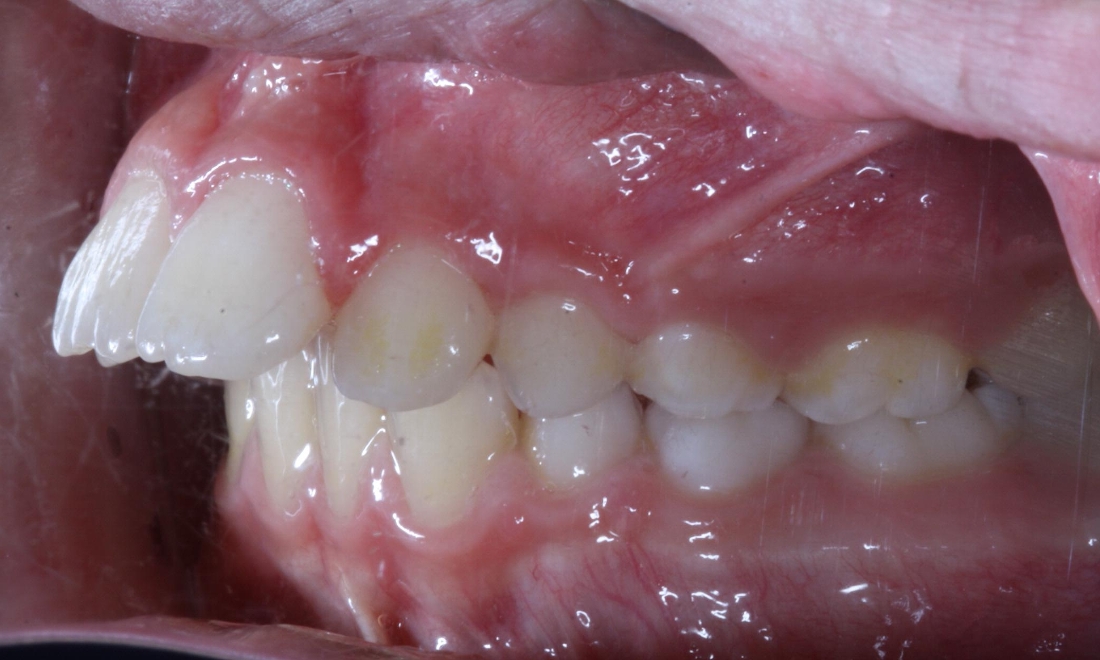

Original Problem: Overjet and Crowding

10 yr old patient with a 10mm overjet- treated with twinblock appliances for 10 months and upper and lower fixed braces afterwards for 20 months.